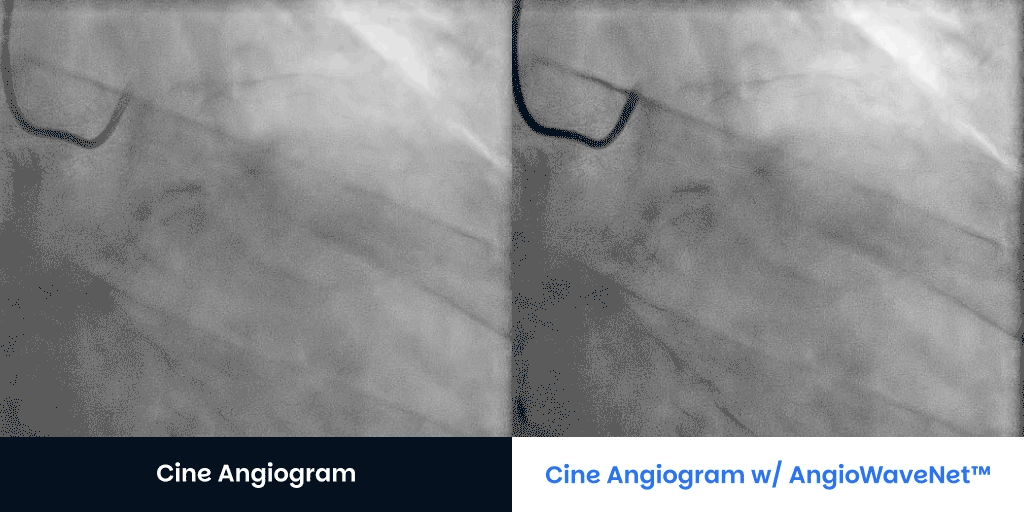

Large Patients BMI > 40 Contact UsGet a Demo CTO Patients Angiograms courtesy of:Jaikirshan Khatri, M.D., Hassan Saleh, M.D. and Weill Cornell Medical Center Left anterior oblique 27°, cranial 1° (unprocessed on left, processed on right) Left anterior oblique 31°, caudal 33° unprocessed on left, processed on right Right anterior oblique 2° caudal 33° (unprocessed on left, processed on right) Right anterior oblique 13°, caudal 36° unprocessed on left, processed on right Contact UsGet a Demo Diagnostic Cine Angiograms Contact UsGet a Demo